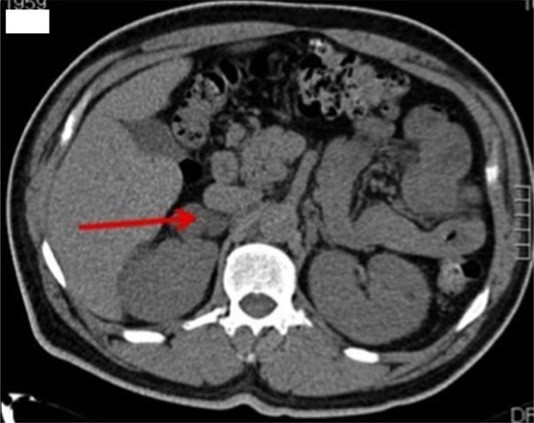

Şekil 2 : Böbrek üstü bezinin sağda iyi huylu adenom (soldaki resim) ve sol böbrek üstü kanserinin (sağdaki resim) tomografik görünümü.